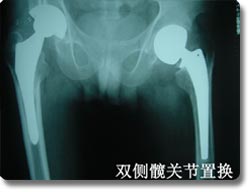

四肢大关节人工关节置换术

关节置换可以说是本世纪骨科手术最伟大的突破之一。目前它已应用於治疗肩关节、肘关节.腕关节、指间关节 、髋关节、膝关节及踝关节等疾患,但以全人工髋关节及膝关节置换最为普遍。对骨关节炎、股骨头无菌性坏死、老年性股骨颈骨折等疾病具有明显治疗效果,我科目前已开展各种置换手术800余例,疗效受到患者普遍肯定。